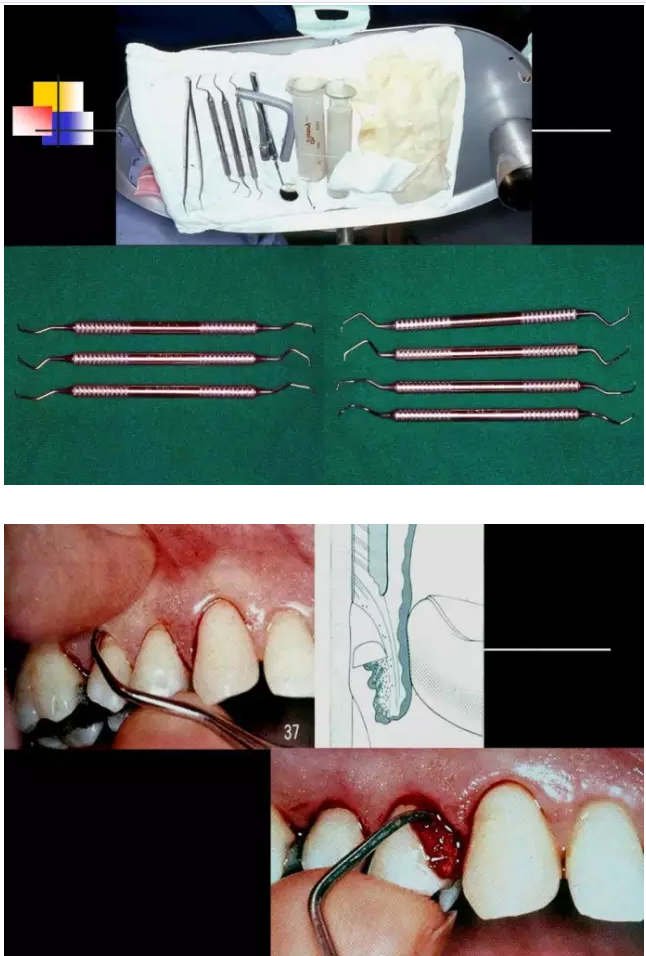

相關(guān)牙周防治